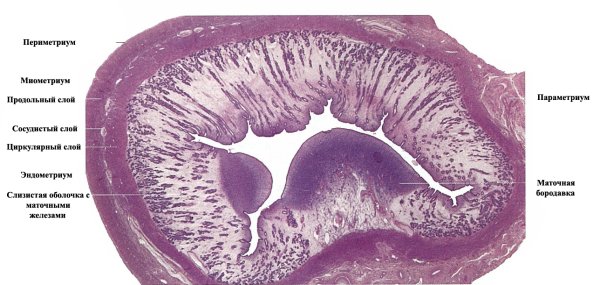

В гистологии матки, также известной как эндометрий, можно наблюдать различные ткани и структуры. На рисунке представлена детальная схема анатомии матки, которая помогает увидеть основные элементы ее строения. Например, это включает в себя миометрий, состоящий из гладкой мышечной ткани, который окружает полость матки, и эндометрий, слой клеток, который выстилает внутреннюю сторону матки. Рисунок также может показывать железистые структуры, которые присутствуют в эндометрии, и кровеносные сосуды, обеспечивающие питание тканей матки. Все эти детали помогают лучше понять анатомию и функции матки, что важно при изучении различных состояний и заболеваний этого органа.

Матка поперечный срез гистология